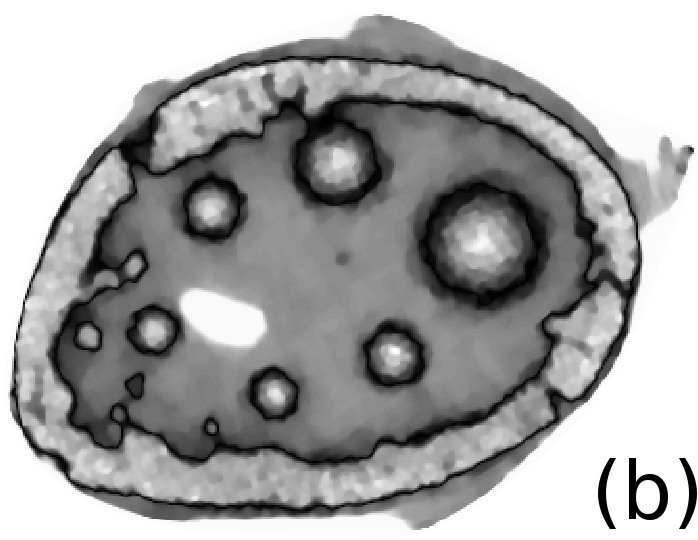

To simulate emission tomography reconstruction we designed a more realistic phantom from the high-quality X-ray scan of a mice bone. The data was acquired on a Nikon Metris Custom Bay cone-beam scanner at the Henry Moseley Manchester X-ray facility, and was reconstructed with the Feldkamp algorithm (see Fig. 7 (left)). We thresholded the obtained reconstruction and added six gaussians with various kernel widths (see Fig. 7 (middle and right)).

To simulate PET projection data we used NiftyRec [22], a software for tomographic reconstruction, providing GPU-accelerated reconstruction for emission and transmission computed tomography. The phantom size is pixels and 300 projections was simulated. Poisson noise was added to projections with an expected number of photon counts in total. Twenty noise realizations were simulated to estimate methods quantitatively. The point spread function of the PET system was modelled (with convolution of the sinogram columns with a Gaussian of full width half maximum of three pixels) in the projection and back-projection operations. No scatter was simulated in this study. For our experiments (see algorithm 2) we performed 130 MLEM iterations and 5 inner iterations (denoising step).

In Fig. 10 and 11 one can notice that the BR is very smooth for TV and TV- penalties and some long-wave oscillations can be seen in the reconstructed image with EL penalty. This result corresponds to the expected behaviour of the EL penalty. We note here that the phantoms background (see Fig. 7) is not as flat as TV and TV- penalty recovered it. Furthermore, a small size dot-like feature (approximately in the centre of the phantom) is almost smoothed out with TV and TV- recovery. However, it is visible and well recovered with EL penalty. The sharp features, overall, are reconstructed very well with MLEM-EL method and seem even sharper compare to other methods (see the bone outer rim in Fig 10).